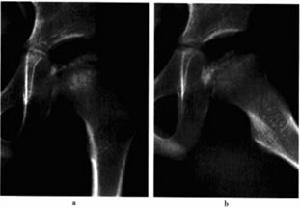

股骨頭壞後圈9-1左股骨頭骨骺缺血性坪死(早期)

A b平片.示左側股骨頭骨骺輕度變扁,密度均勻增高,乾骺端增寬,鄰骺線處出現帶狀低密度區。